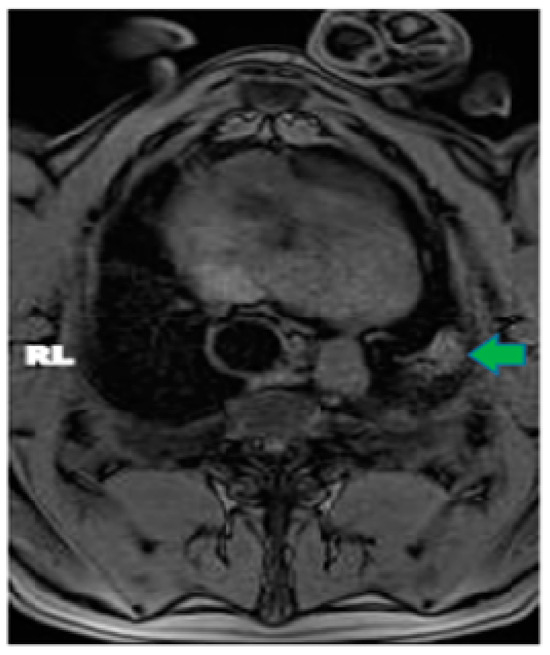

In pig #2, the aim was to study the health effects following MRgFUS with multiple (six) doses of a higher power delivered at six different locations but using only two intercostal/skin areas as entry points. Following the six treatments with MRgFUS at 350 Watts for 20 s each, mild burn marks were visible on the skin at the FUS beam entry points. The pig recovered successfully from the anesthesia. Mild wheezing was noticeable in the week-long post-treatment follow-up. After one week, the pig was scanned using MRI and had hyper-intense regions in the left lung that corresponded with the treatment locations (an example is shown Figure 2). The pig was then euthanized and examined utilizing gross histology. At the locations of the MRgFUS treatment, there were dense fibrotic tissues with white discoloration, indicating successful lung parenchyma ablation (Figure 3A). There was no damage observed on the pericardium or heart.

Figure 2. Axial MRI view of pig #8, one-week post MRgFUS ablation treatment. Green arrow points to ablated area in left lung.